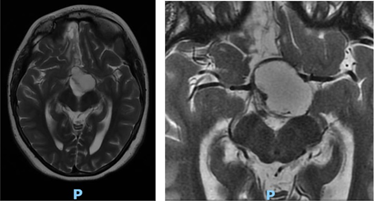

That lesion partially compressed the 3rd ventricle, displaced the optic chiasm anteriorly and extended posteriorly occupying the interpeduncular and prepontine cistern. Associated with a small hyperintense nodular image on T1 at the level of the 3rd ventricle (Figure 4). Considering the clinical picture, the changes in the MRI and its history, it was interpreted as a recurrence of Craniopharyngioma. In conjunction with neurosurgery, surgical removal of the tumor was decided, with placement of a ventriculoperitoneal shunt valve. Systemic treatment with corticosteroids, hormone replacement drugs and external radiotherapy was established. After a year, she attended a new ophthalmological control, presenting cushingoid facies. On examination, BCVA was 20/40 in both eyes. She presented exotropia, with hypertropia of the left eye with limited infraduction (Figure 5). She preserved photomotor and consensual pupillary reflex in the right eye, while in the left eye she manifested areactive mydriasis. On examination of the fundus, bilateral papilla atrophy was observed (Figure 6). The visual field also showed clinical improvement, with sequelae bitemporal heteronymous hemianopsia (Figure 7). The OCT did not present significant changes in the fiber layer (Figure 8). The axial section of the nuclear magnetic resonance showed, on T1 sequence, that an area with a sequelae aspect persisted at the level of the center-medial nucleus of the left thalamus, interpreted as evolving ischemia (Figure 9).

Figure 4 Contrast-enhanced axial T2-weighted nuclear magnetic resonance imaging (preoperative).